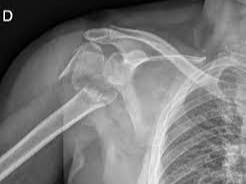

어깨 주변 골절은 단순히 뼈가 붙는 시간만으로 설명하기 어려운 손상입니다. 많은 분들이 “어깨뼈 골절 통증기간이 얼마나 되나”, “상완골 골절로 수술하면 입원을 며칠이나 하나”를 가장 먼저 궁금해하시지만, 실제 임상에서는 골절 부위가 견갑골인지, 상완골 근위부인지, 골절선이 단순한지 분쇄형인지, 수술을 했는지, 다른 장기나 뼈의 동반 손상이 있는지에 따라 통증과 회복 곡선이 크게 달라집니다. 특히 어깨는 관절 가동범위가 넓은 대신 한번 다치면 강직이 쉽게 생기는 부위라서, 통증이 줄어드는 시점과 일상 기능이 회복되는 시점이 서로 다를 수 있습니다.

일반적으로 어깨 주변 골절은 뼈가 붙는 데 약 6주에서 12주 정도가 걸리고, 실제 움직임과 근력 회복은 수개월 더 이어질 수 있습니다. 견갑골 골절은 다수에서 보존적 치료가 가능하지만, 상완골 특히 근위 상완골 골절은 변위 정도에 따라 고정술이나 인공관절수술까지 고려되기도 합니다. 따라서 통증기간만 단정적으로 묻기보다, 골절의 형태와 치료방식을 함께 이해하는 것이 현실적입니다.